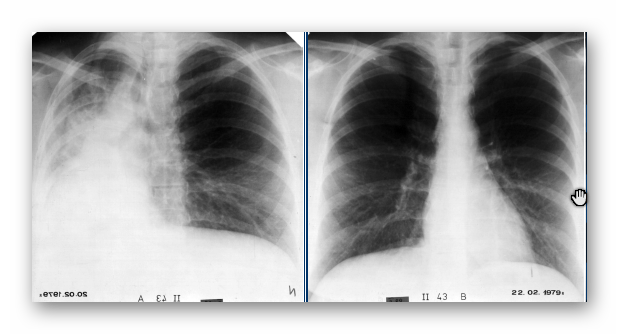

NIEDODMA

RTG

(OBRAZ PRZED I PO USUNIĘCIU CZOPA ŚLUZOWEGO)